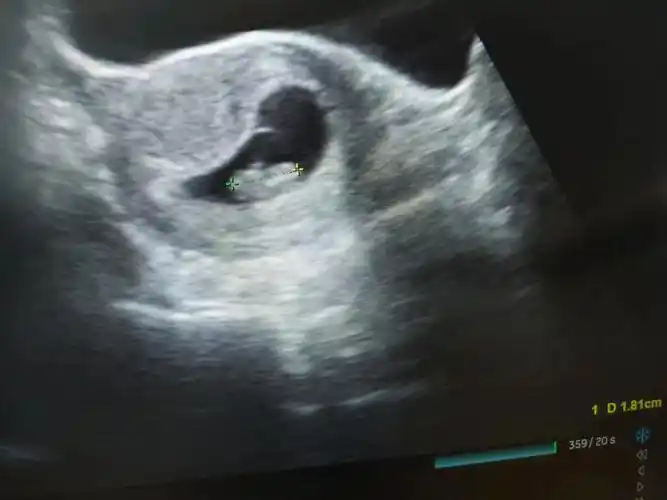

孕7周1天胎心胎芽正常

胎心胎芽